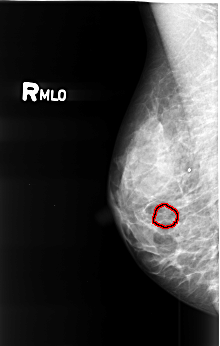

B_3422_1.RIGHT_MLO

RIGHT_MLO LINES 4496 PIXELS_PER_LINE 2856 BITS_PER_PIXEL 12 RESOLUTION 50 OVERLAY

FILE: B_3422_1.RIGHT_MLO.OVERLAY

TOTAL_ABNORMALITIES 1

ABNORMALITY 1

LESION_TYPE CALCIFICATION TYPE PLEOMORPHIC DISTRIBUTION CLUSTERED

ASSESSMENT 4

SUBTLETY 3

PATHOLOGY BENIGN

TOTAL_OUTLINES 1

BOUNDARY